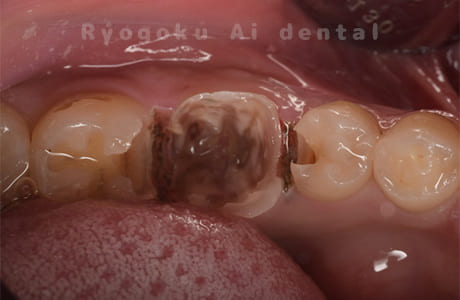

Case02

-

- 原因

- C4

- 治療期間

- 3ヶ月

- 治療内容

- 自家歯牙移植手術+マイクロエンド+ダイレクトボンディング

- 治療費用

- 220,000円

他院で虫歯が大きく、抜歯と判断され、インプラント手術を提案された患者様です。親知らずが残存していたため、自家歯牙移植手術を行いました。

<リスク・副作用>

治療後、痛みや違和感、出血、腫れなどが出る事があります。喫煙者、糖尿病などの方の場合、歯が生着しない場合があります。